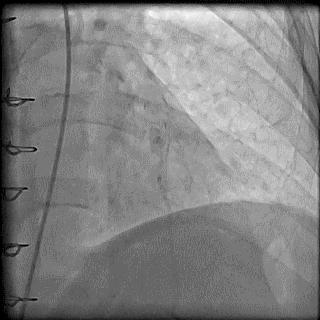

(1)导管总进圆锥动脉

➢ CASE 8

必要时更换导管,避免并发症的发生